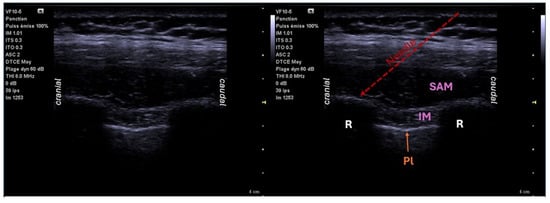

6.4. Serratus Block